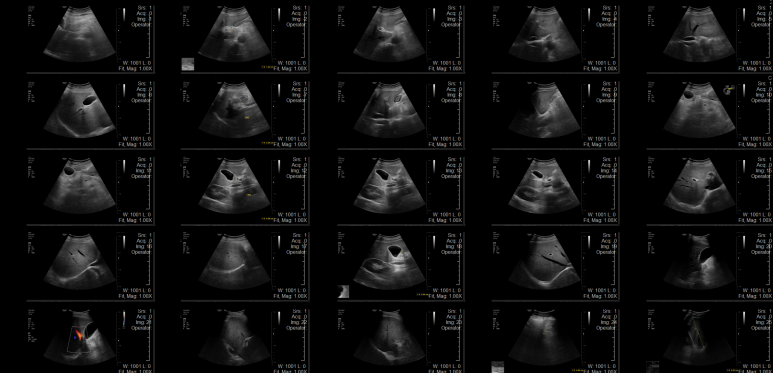

60대 초반 남자, 1년전 공무원 검진으로 초진 rGTP가 매우 높아 음주량 확인하니 매일 맥주 1,600 cc 당시 초음파 시행, 종양성 병변이 없는 것을 확인하고 발부 1년후 재내원... 비슷할것 같은데? rGTP가 1516 음주량은? 일주일에 3~4번이라고 하나... 몸에서는 반응하는듯 초음파는 기존과 같이 지방간 좌엽에 약간의 위축정도가 보이는... 이런 소견이 뚜렷하지는 않았다. 지난 한달간 진행한 섬유화/간경화 방향의 설명.. : 네이버블로그 그러나, 음주를 계속한다면? 아래의 경우가 떠오르는데... AST/ALT 및, rGTP가 매년 상승 https://blog.naver.com/ejercicio/222279372093 최근 7년간 끊지 못하고 간의 모양이 변하다가 복수까지 찬 경우가 있다. 금주하지 못하는 알콜성 간경화 환자에서 드디어.. : 네이버블로그 며느리가 이뻐서 이렇게도 하는데 3살된 손자가 귀하다면? 할아버지가 바뀔 필

복부 초음파; 초음파에서 위벽 비대 및 복수 소견, 내시경으로 진행성 위암 확인, 기타 잘 살피지 않으면 놓칠 수 있는 위선종

초음파에서 위벽 비대 및 복수 소견, 내시경으.. : 네이버블로그 동대문구 답십리 우리안애, 우리안愛 내과, 초음파 클리닉, 영상의학 클리닉, 내과 전문의 전병연 #동대문구내과 #성동구내과 #광진구내과 #답십리역 #장안평역 #용답역 #청량리역 #신답역 #한양대역 #왕십리역 #답십리사거리 #촬영소사거리 #전농동사거리 #내과 #국가검진 #위내시경 #대장내시경 #갑상선초음파 #복부초음파 #경동맥초음파 #심장초음파 #암검진 #래미안위브아파트 #엘림스퀘어 #두산아파트 #동아아파트 #한양아파트 #동답한신아파트 #두산위브아파트 #힐스테이트청계아파트 #래미안미드카운티 #청솔우성 #래미안크레시티 #롯데캐슬노블레스 #e편한세상답십리아르테포레

복부, 간초음파; 만성 음주자에서 명확해진 알콜성 간경화, 혈액검사 및 초음파 등 종합적 판단

만성 음주자에서 명확해진 알콜성 간경화, 혈액.. : 네이버블로그 동대문구 답십리 우리안애, 우리안愛 내과, 초음파 클리닉, 영상의학 클리닉, 내과 전문의 전병연 #동대문구내과 #성동구내과 #광진구내과 #답십리역 #장안평역 #용답역 #청량리역 #신답역 #한양대역 #왕십리역 #답십리사거리 #촬영소사거리 #전농동사거리 #내과 #국가검진 #위내시경 #대장내시경 #갑상선초음파 #복부초음파 #경동맥초음파 #심장초음파 #암검진 #래미안위브아파트 #엘림스퀘어 #두산아파트 #동아아파트 #한양아파트 #동답한신아파트 #두산위브아파트 #힐스테이트청계아파트 #래미안미드카운티 #청솔우성 #래미안크레시티 #롯데캐슬노블레스 #e편한세상답십리아르테포레